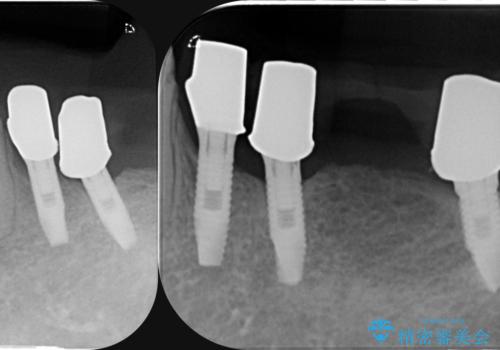

虫歯による歯の喪失 インプラントによる咬合機能回復

- 深い虫歯や歯の破折、多数の問題を口腔内に抱えて来院されました。

虫歯の徹底的な除去、安定した噛み合わせを達成するインプラント治療、深い虫歯、根管治療といった複数の治療項目を一つづつ積み重ね、長期的な予後を目指します。

複雑な問題点に対する明確な治療目標を立てることで、最終的に長い予後を期待できる治療を達成することができます。